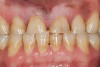

Figure 2   Asymmetric tooth wear in a bruxism triad patient as a result of friction from bruxing, poor salivary lubrication as a byproduct of medication, and roughened surfaces created as a result of erosive reflux.

Figure 2

The study of tooth wear is appropriately described as tribology: the science of interacting surfaces in relative motion and associated issues of lubrication, friction, and wear. Teeth sliding over each other are affected by a complex tribological interaction. Friction is encountered whenever there is relative motion between contacting surfaces, and it always opposes the motion. As no surface is perfectly smooth, when the teeth make contact, even under light load, it may produce the loss of tooth structure. When non-roughened surfaces contact, their coefficient of friction decreases dramatically if a lubricant is introduced. Tribology would suggest that a decrease in oral lubrication coupled with tooth-on-tooth contact would introduce friction and, thus, wear.12 In addition, elements that increase the surface roughness (eg, erosion) would unavoidably increase wear (Figure 2).